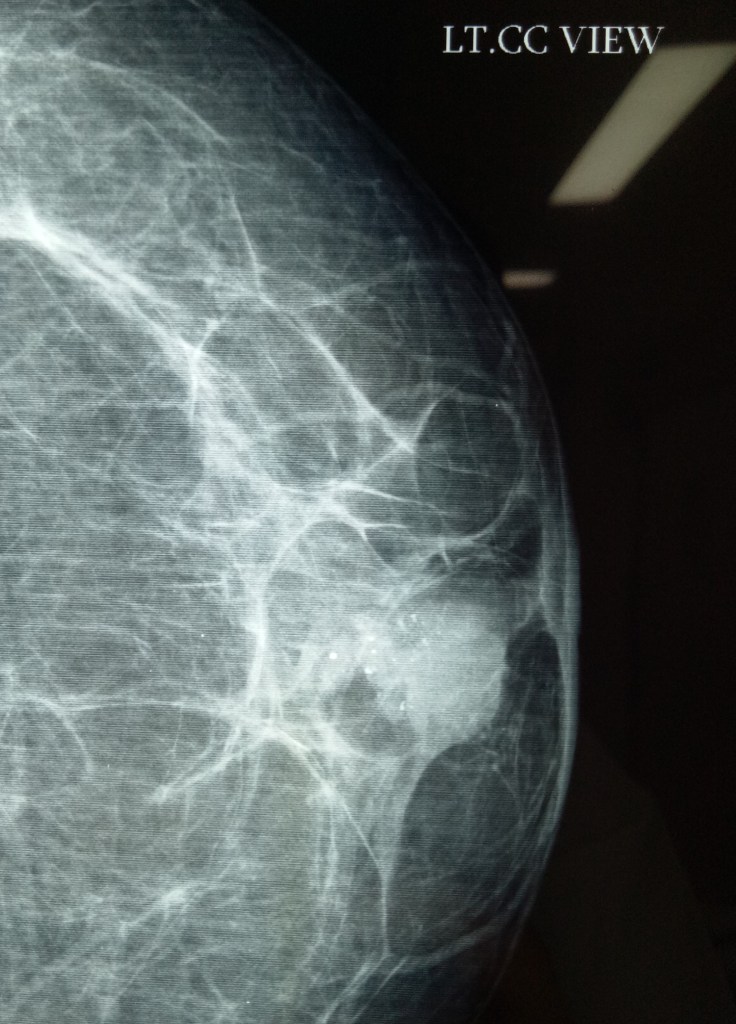

3.6.21

MRM for lobular carcinoma of breast (Dr Jagga’s case). Small tumor (less than 4 cm) and not expected to have metastases in axillary lymph nodes (which were not palpable) actually turned out to have a mass of several enlarged lymph nodes during axillary exploration.